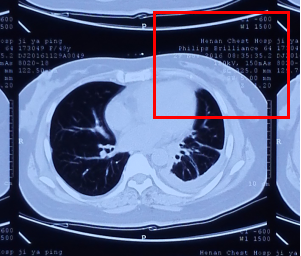

2、要正确识别片子的翻正:在片子的每个小图像(小方格)上都有数字或英文字母,只要这些内容是正立的,那么片子就“正”了。如下图红色方框内字母数字:

下图即是一个质量较好的拍摄照片: